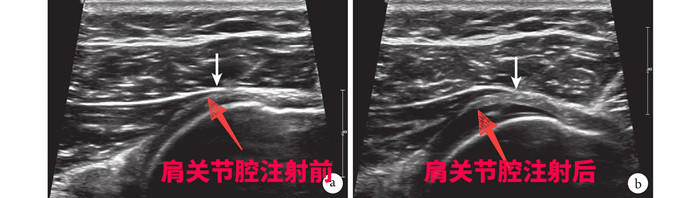

針對(duì)劉大爺?shù)那闆r,徐慧勝制定了個(gè)性化治療方案“體外沖擊波結(jié)合超聲引導(dǎo)下肩關(guān)節(jié)注射治療”,先采用沖擊波松解肩關(guān)節(jié)周圍黏連的組織,然后在超聲引導(dǎo)下將消炎鎮(zhèn)痛液準(zhǔn)確注射到肩關(guān)節(jié)腔、滑囊及神經(jīng)周圍,起到雙管齊下的作用。15分鐘后,劉大爺感覺疼痛減輕了大半,活動(dòng)明顯改善。經(jīng)過(guò)3次治療,劉大爺?shù)募缰苎滓鸦局斡?